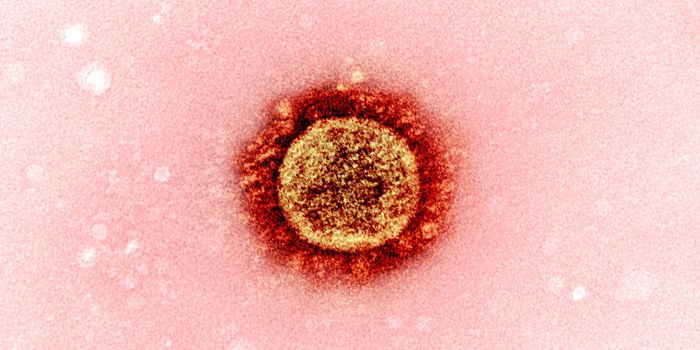

JUL 11, 2021MicrobiologyIn October 2020, what's now called the Delta variant of SARS-CoV-2 was first detected. It's now the most prevalent strai ...

NOV 01, 2021Cell & Molecular BiologyResearchers have learned a lot about the SARS-CoV-2 virus since the start of the COVID-19 pandemic. We know that he viru ...

SEP 07, 2021MicrobiologyThe world has rapidly become familiar with sarbecoviruses, two of which jumped to humans in recent years. The first was ...